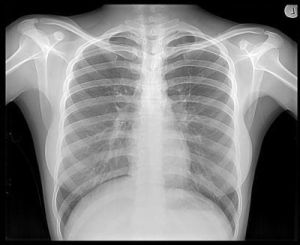

手部x光片 1895年11月8日傍晚,他研究陰極射線。為了防止外界光線對放電管的影響,也為了不使管內的可見光漏出管外,他把房間全部弄黑,還用黑色硬紙給放電管做了個封套。為了檢查封套是否漏光,他給放電管接上電源(茹科夫線圈的電極),他看到封套沒有漏光而滿意。可是當他切斷電源後,卻意外地發現一米以外的一個小工作檯上有閃光,閃光是從一塊螢光屏上發出的。然而陰極射線只能在空氣中進行幾個厘米,這是別人和他自己的實驗早已證實的結論。於是他重複剛才的實驗,把屏一步步地移遠,直到2米以外仍可見到屏上有螢光。倫琴認為這不是陰極射線了。倫琴經過反覆實驗,確信這是種尚未為人所知的新射線,便取名為X射線。他發現X射線可穿透千頁書、2~3厘米厚的木板、幾厘米厚的硬橡皮、15毫米厚的鋁板等等。可是1.5毫米的鉛板幾乎就完全把X射線擋住了。他偶然發現X射線可以穿透肌肉照出手骨輪廓,於是有一次他夫人到實驗室來看他時,他請她把手放在用黑紙包嚴的照相底片上,然後用X射線對準照射15分鐘,顯影后,底片上清晰地呈現出他夫人的手骨像,手指上的結婚戒指也很清楚。這是一張具有歷史意義的照片,它表明了人類可藉助X射線,隔著皮肉去透視骨骼。1895年12月28日倫琴向維爾茨堡物理醫學學會遞交了第一篇X射線的論文“一種新射線——初步報告”,報告中敘述了實驗的裝置,做法,初步發現的X射線的性質等等。X射線的發現,又很快地導致了一項新發現——放射性的發現。